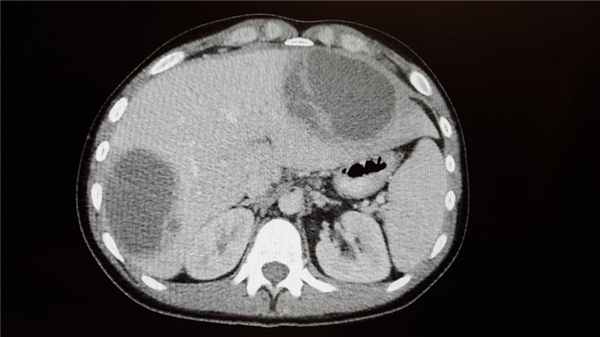

Абсцесс печени чаще всего возникает в результате распространения инфекции по сосудистому руслу из воспалительных очагов других органов или тканей брюшной полости (аппендицит, холангит, язвенный колит). Абсцессы могут быть одиночными или множественными. Для заболевания характерна высокая температура, озноб, боль и тяжесть в области печени, увеличение ее размеров.

Абсцесс в печени

Абсцессы брюшной полости встречаются в 30-35% у больных гнойным перитонитом. Обычно они располагаются в отлогих областях живота: подпеченочном, поддиафрагмальном пространстве, в подвздошных ямках и т.п. Клинике формирования абсцесса соответствует ухудшение состояния после небольшого светлого промежутка на фоне воспалительного заболевания брюшной полости (аппендицита, холецистита), наблюдается усиление интоксикации и боль в животе.